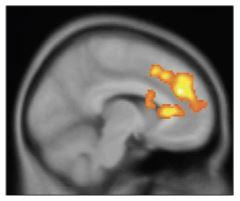

A drug being studied as a fast-acting mood-lifter restored pleasure-seeking behavior independent of – and ahead of – its other antidepressant effects, in a National Institutes of Health trial. Within 40 minutes after a single infusion of ketamine, treatment-resistant depressed bipolar disorder patients experienced a reversal of a key symptom – loss of interest in pleasurable activities – which lasted up to 14 days. Brain scans traced the agent's action to boosted activity in areas at the front and deep in the right hemisphere of the brain.

Next, the researchers scanned a subset of the ketamine-infused patients, using positron emission tomography (PET), which shows what parts of the brain are active by tracing the destinations of radioactively-tagged glucose – the brain's fuel. The scans showed that ketamine jump-started activity not in the middle brain area they had expected, but rather in the dorsal (upper) anterior cingulate cortex, near the front middle of the brain and putamen, deep in the right hemisphere.

Boosted activity in these areas may reflect increased motivation towards or ability to anticipate pleasurable experiences, according to the researchers. Depressed patients typically experience problems imagining positive, rewarding experiences – which would be consistent with impaired functioning of this dorsal anterior cingulate cortex circuitry, they said. However, confirmation of these imaging findings must await results of a similar NIMH ketamine trial nearing completion in patients with unipolar major depression.